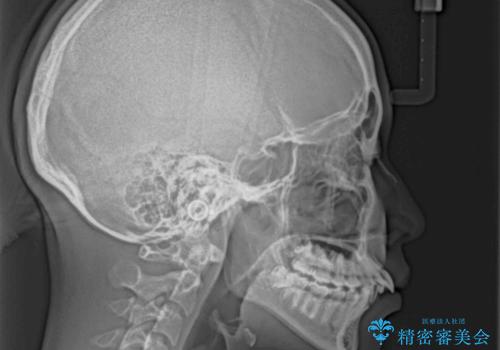

指が入るくらいに隙間のある上下前歯 抜歯矯正で横顔の印象が大きく改善

- 上顎前歯の突出感を気にして来院された患者様です。

舌の突出癖などにより、上下前歯の間に指が入るくらい隙間のできる状態でした。

下顎は叢生があったため、上下左右の第一小臼歯4本を抜歯し、更には口元の突出感を大きく改善させるために、上顎臼歯を後方に移動させるための補助装置をしようし、ワイヤー装置にて矯正治療を行うこととしました。